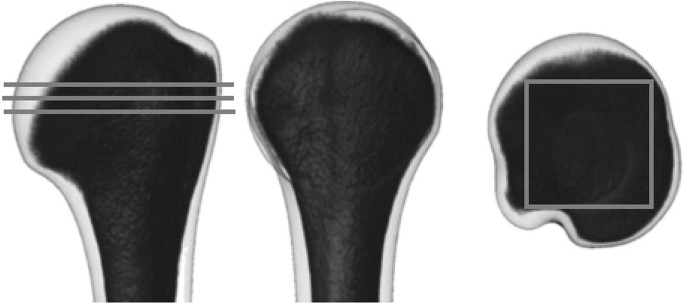

Quantitative computed tomography was used to measure bone mineral density (BMD) of each humeral head. BMD was evaluated at the greatest transverse diameter of the humeral head along three parallel sections separated by 1.5-mm distance15. The square region of interest (ROI) was positioned over the bone slice so that every edge of the square could reach the subcortical shell of the humeral head. The mean BMD of the three slices was used15. (Fig. 1).